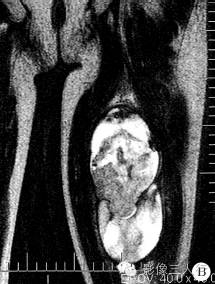

病理诊断:瘤体血管丰富呈鹿角状分支,管腔不规则,管壁薄;瘤细胞呈卵圆形或短梭形,胞质少;细胞核呈圆形或卵圆形,染色深,核分裂易见;瘤细胞围绕血管分布;免疫标记提示瘤细胞中度增殖。病理诊断为恶性血管外皮瘤。

文献报道,血管外皮肉瘤发现时多体积巨大,平均直径8〜10cm。因肿瘤内有坏死、囊变区及纤维组织成分,血管外皮肉瘤在MRI图像上多信号混杂,T1WI为等低信号为主,T2WI不均匀高信号,可伴瘤体内出血。50%以上的血管外皮肉瘤瘤内有扭曲的血管流空征象,可作为该病的特征性表现。但是,海绵状血管瘤和部分恶性纤维组织细胞瘤,因血管丰富,也可有血管流空征象,与之鉴别有困难。